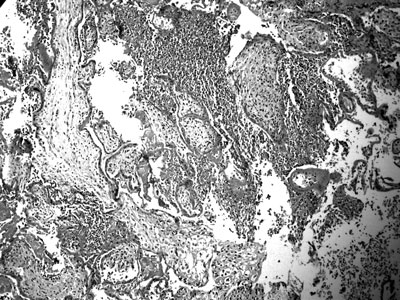

Εικόνα 3. Oξεία μεσολαχνίτιδα. Oξεία φλεγμονώδης διήθηση του μεσολάχνιου χώρου με ουδετερόφιλα πολυμορφοπύρηνα (Χρώση αιματοξυλίνης- ηωσίνης. Αρχική μεγέθυνση 100).

Λαχνίτιδα. Σε λίγες μόνο περιπτώσεις λαχνίτιδας οφειλόμενης σε ιούς, βακτήρια ή πρωτόζωα αναγνωρίζονται χαρακτηριστικά ιστολογικά ευρήματα ενδεικτικά του λοιμώδους παράγοντα.(24) Ιογενείς λοιμώξεις, όπως AIDS, λοίμωξη από Coxsackie ιό ή ηπατίτιδα, δεν προκαλούν ιδιαίτερες αλλοιώσεις στον πλακούντα. Αντίθετα, η οξεία μεσολαχνίτιδα ή περιλαχνίτιδα είναι ενδεικτική λοιμώδους αιτιολογίας (εικόνα 3).(25)